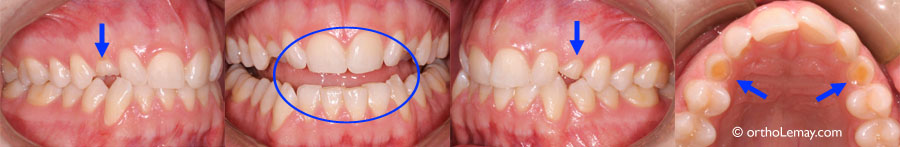

Asymétrie importante causée par l’extraction de prémolaires sans supervision subséquente. (A et B) L’extraction d’une prémolaire supérieure et inférieure du côté droit (flèche) a causé le déplacement des dents antérieures vers la droite. La ligne pointillée montre l’importance de la déviation. (C) La mandibule et le menton sont aussi déviés vers la droite. La ligne jaune est alignée avec les incisives centrales supérieures décalées vers la droite. (D) La déviation des dents affecte l’esthétique du sourire. (E) Les flèches indiquent les endroits où les dents ont été extraites.

Extraction d’une prémolaire supérieure droite (flèche) ayant créé une asymétrie importante à l’arcade supérieure.

Malocclusion sévère (béance antérieure et postérieure, constriction maxillaire, chevauchement dentaire, asymétrie). Une prémolaire supérieure gauche fut extraite en bas âge (flèches bleues), les dents supérieures ont dévié de ce côté, exacerbant l’asymétrie de la ligne médiane (A et B – flèches jaunes et ligne rouge), n’améliorant aucunement la sévérité de la malocclusion, l’esthétique ou la fonction. Ce cas requiert toujours une intervention orthodontique majeure, mais l’orthodontiste doit en plus composer avec une asymétrie plus importante.

Extraction de 3 prémolaires (indiquées par les flèches), déviation des lignes médianes et migration incontrôlée des dents. Il y a autant de chevauchement dentaire et de problèmes d’occlusion malgré l’extraction de 3 dents qui “devaient régler le problème”. La canine supérieure gauche (*) est toujours aussi croche et manque d’espace malgré ces extractions!

Les flèches bleues indiquent les endroits où les 3 prémolaires ont été extraites.

Les lignes bleues indiquent les lignes médianes (milieu des arcades).

Les flèches rouges indiquent la direction de migration des lignes médianes et de la canine supérieure gauche (*) qui a avancé par-dessus l’incisive latérale.

La ligne rouge (D) indique l’asymétrie résultante à l’arcade inférieure; il y a 2 prémolaires à gauche et une seule à droite.